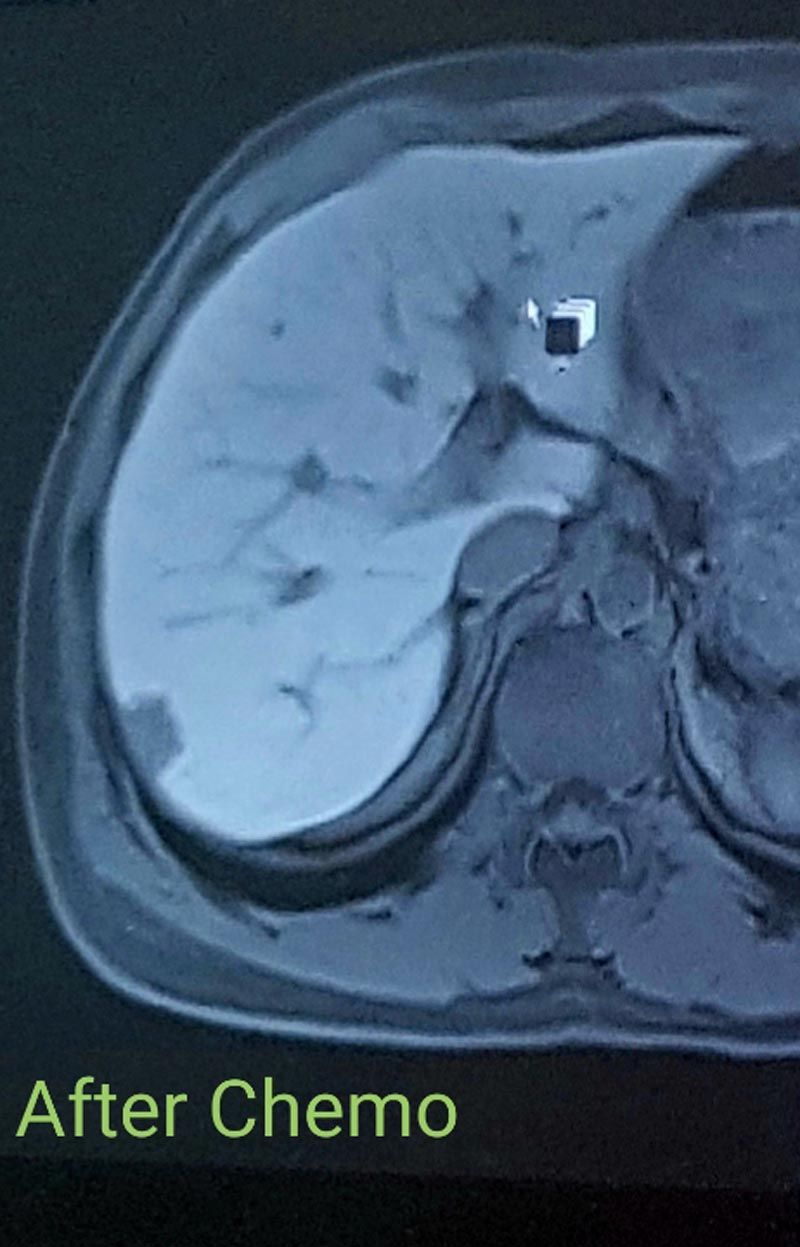

“Chemo completely wiped me out. But, at the end of the three months, I was rescanned and it had done its job."

“The tumors in my liver had reduced enough for doctors to be able to operate."

Four weeks later, on May 15, Reece had 65 per cent of his liver removed in a five hour long operation with a specialist surgeon at Basingstoke and North Hampshire Hospital.